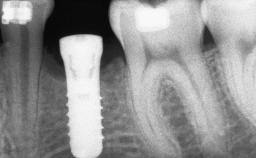

Bone Volume Deficient vertically or deficient vertically AND horizontally